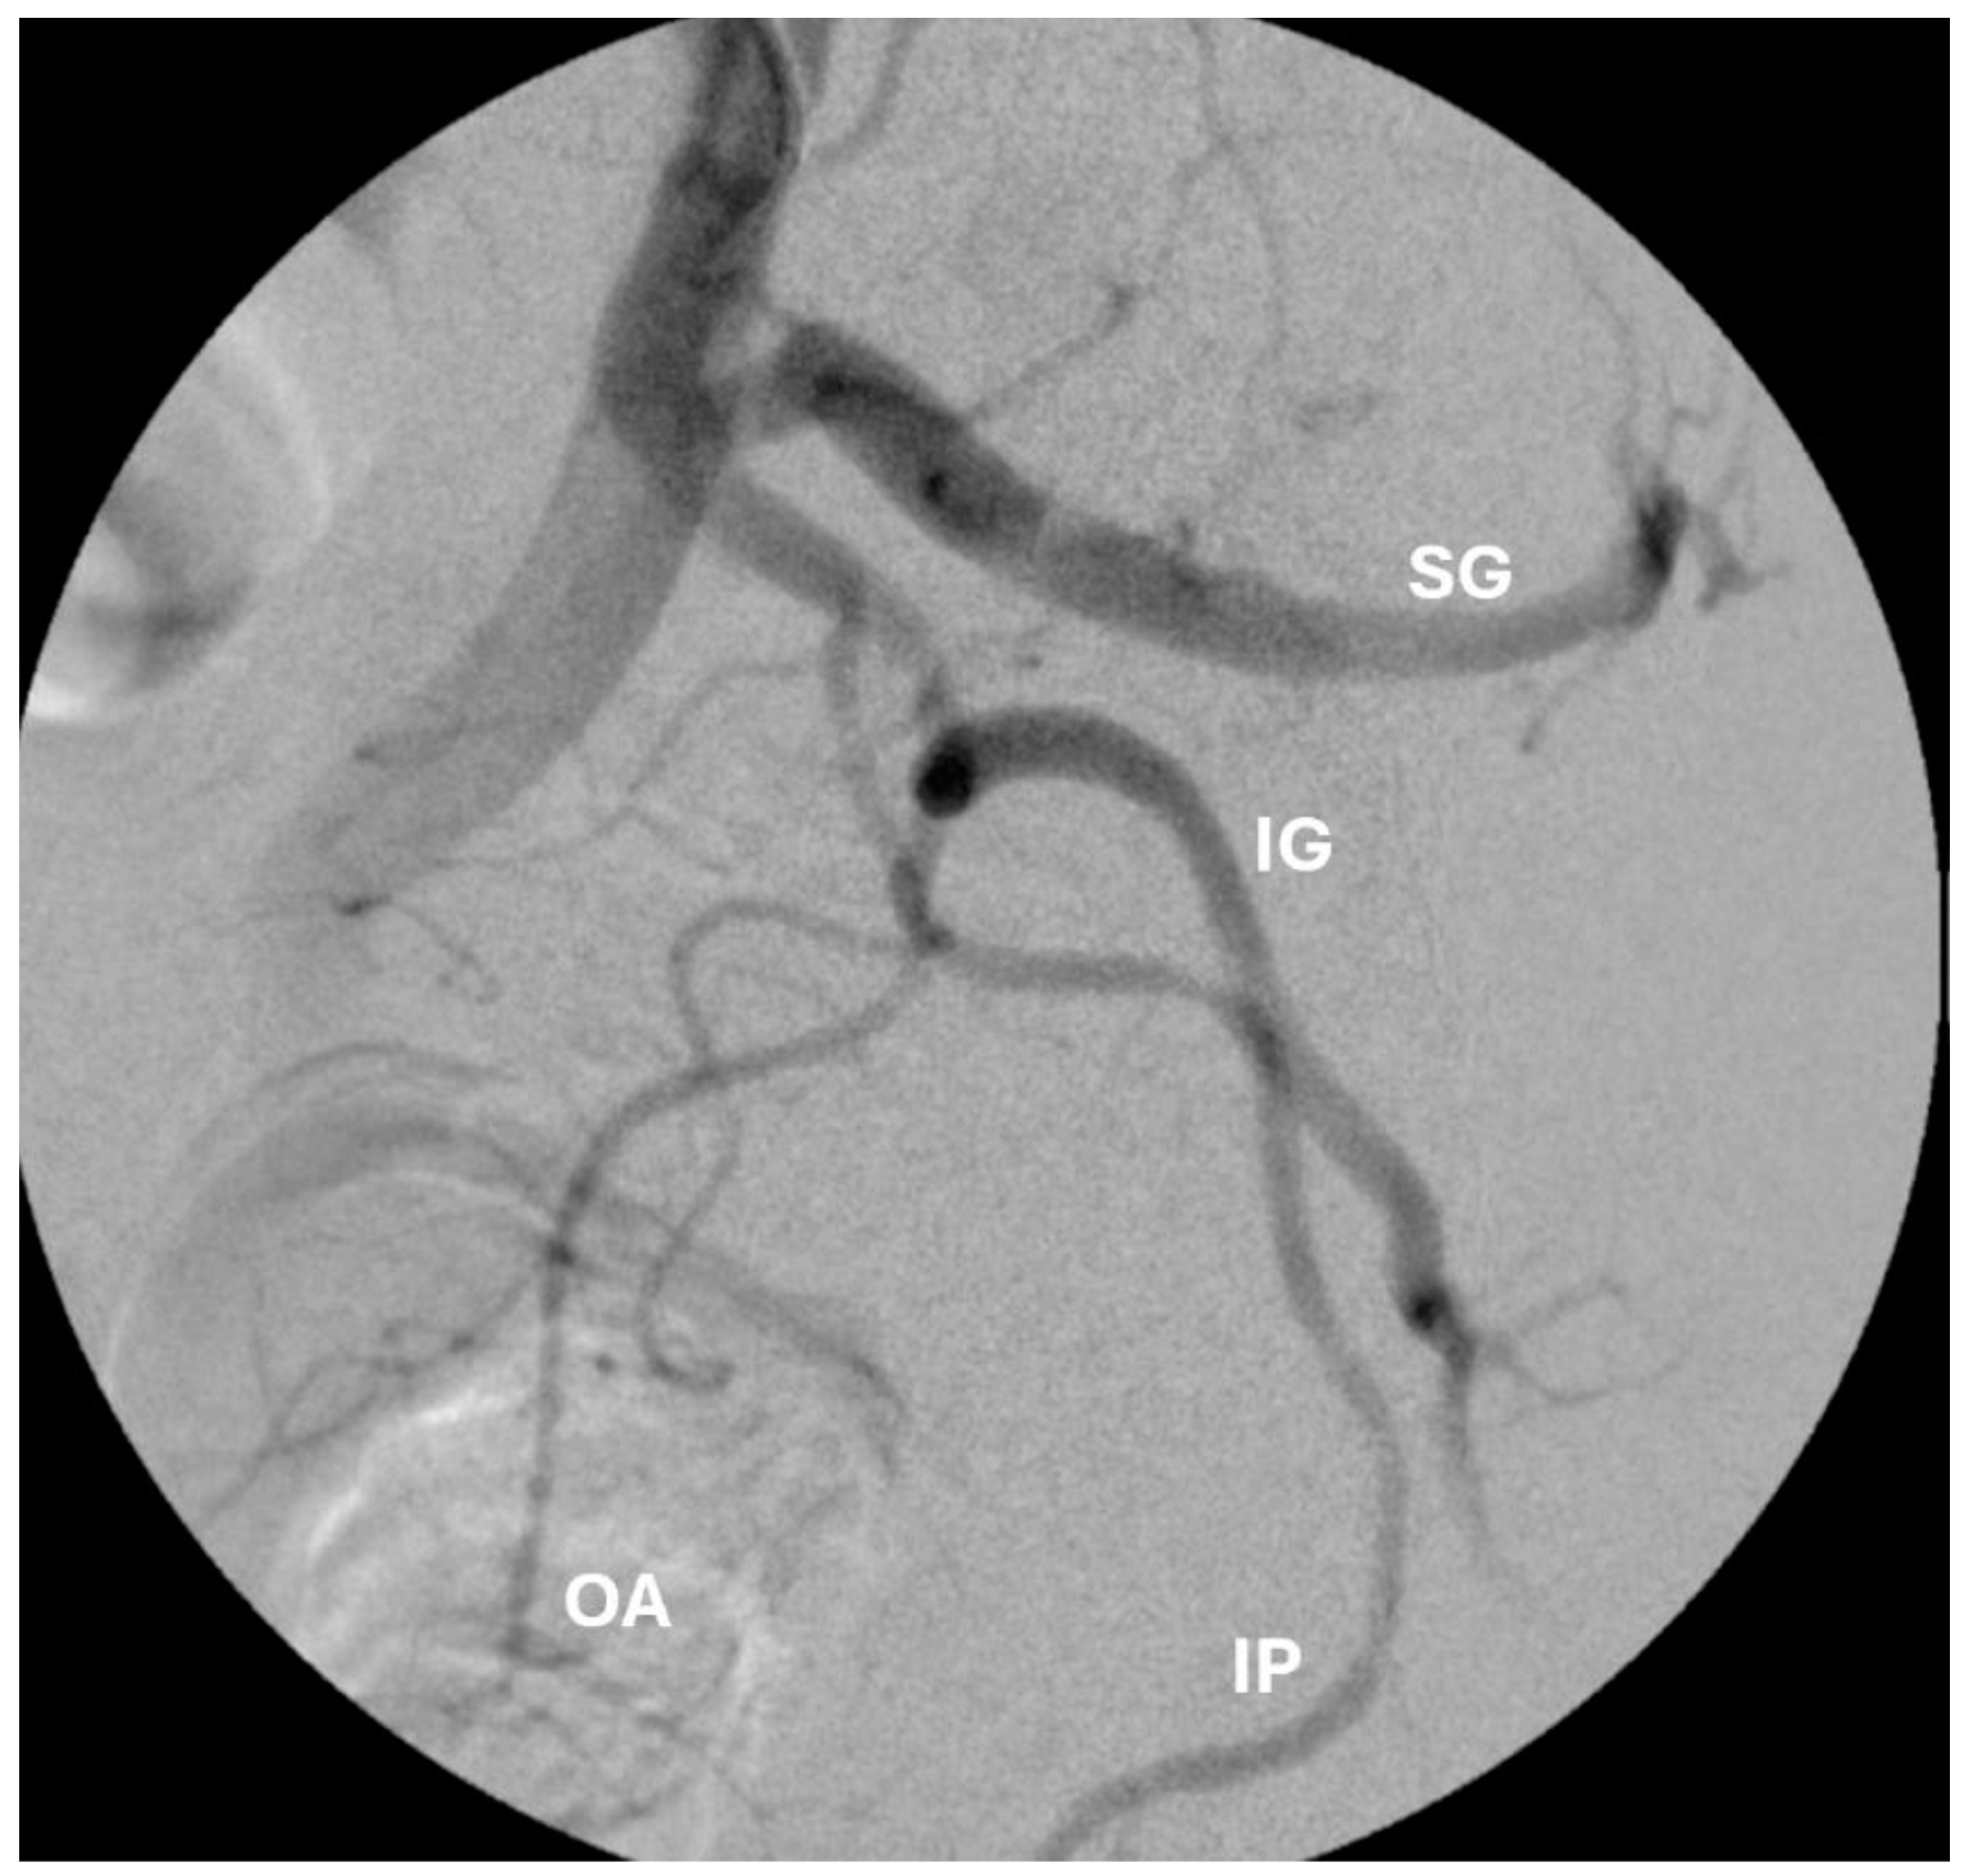

Figure 3.

Angiogram of the internal illiac artery demonstrating the relevant prostate artery embolization anatomy. SG: superior gluteal. IG: inferior gluteal. IP: internal pudendal. OA: obturator artery.